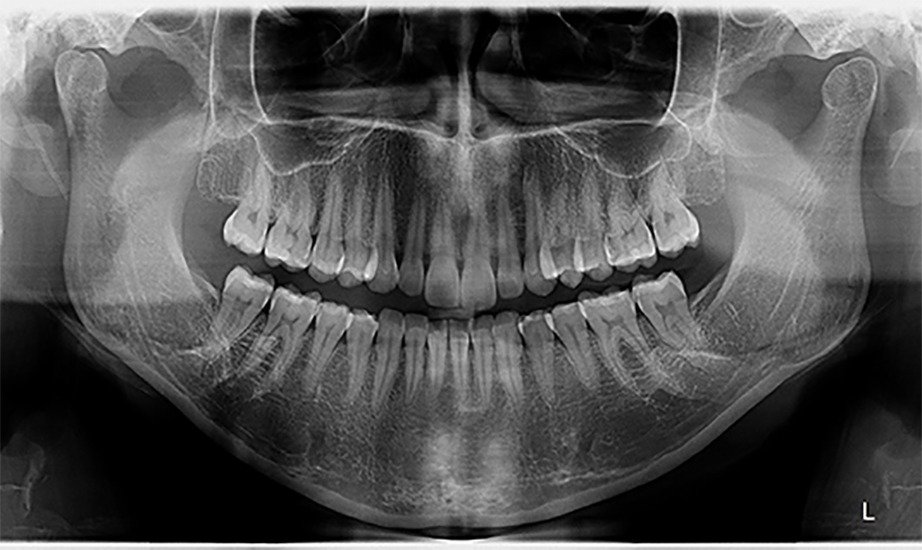

Uma radiografia panorâmica (ou ortopantomografia) fornece uma imagem bidimensional (2D) ampla e única que abrange toda a estrutura bucomaxilofacial. Ela é fundamental para o diagnóstico geral e planejamento de tratamentos, mostrando de uma só vez os dentes, maxilares e articulações.

Oferecemos infraestrutura completa para Tomografia 3D, Documentação Ortodôntica completa e exames de rotina como Panorâmica e Telerradiografia. Somos o braço direito dos dentistas da região, entregando imagens de alta definição para planejamentos de implantes e ATM, garantindo que profissionais e pacientes tenham a segurança e a clareza que merecem.